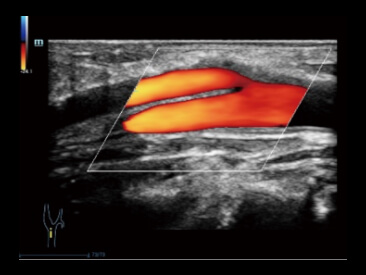

Potenciada por la tecnologĂa ZST+ y la ecografĂa de contraste mejorada (CEUS) basada en ondas planas, la HiFR CEUS permite que la ecografĂa de contraste mejorada ultrarrĂĄpida, para la visualizaciĂłn de la estructura vascular y perfusiĂłn en fase arterial, funcione como una herramienta complementaria de UWN+ (ultra-wideband nonlinear contrast imaging).

Caso HiFR CEUS: HNF de hĂgado

*No se recomienda aplicar HiFR CEUS en fase de retardo o en una regiĂłn de 10 cm de profundidad